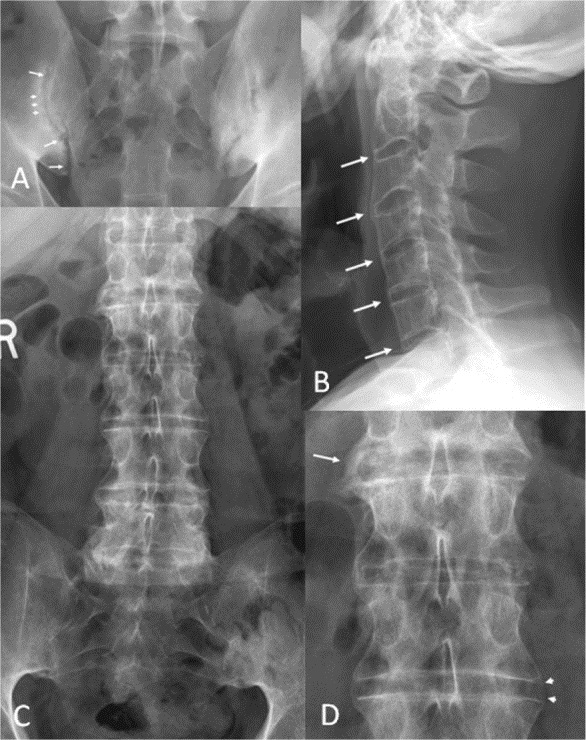

На поздних стадиях болезни Бехтерева происходит слияние позвонков и их окостенение. Это явление хорошо видно на рентгеновских снимках. Во время обострений пациенты испытывают сильные боли, которые мешают нормальному сну. В период ремиссии состояние улучшается, и такие фазы могут длиться несколько месяцев.

При болях в пояснице рекомендуется провести рентгенографию для подтверждения или опровержения болезни Бехтерева. Также могут быть назначены магнитно-резонансная томография (МРТ) и компьютерная томография (КТ). МРТ позволяет визуализировать воспалительные процессы, оценить характер поражения суставов и определить степень распространенности заболевания. На изображении показан позвоночник на МРТ в период обострения недуга.

Возможно проведение ультразвукового исследования (УЗИ), которое помогает точно установить диагноз и определить стадию заболевания. Рекомендуется сдать анализы крови, включая общий, биохимический и на скорость оседания эритроцитов (СОЭ). В некоторых случаях генетики могут назначить тест для выявления антигена HLA-В27.